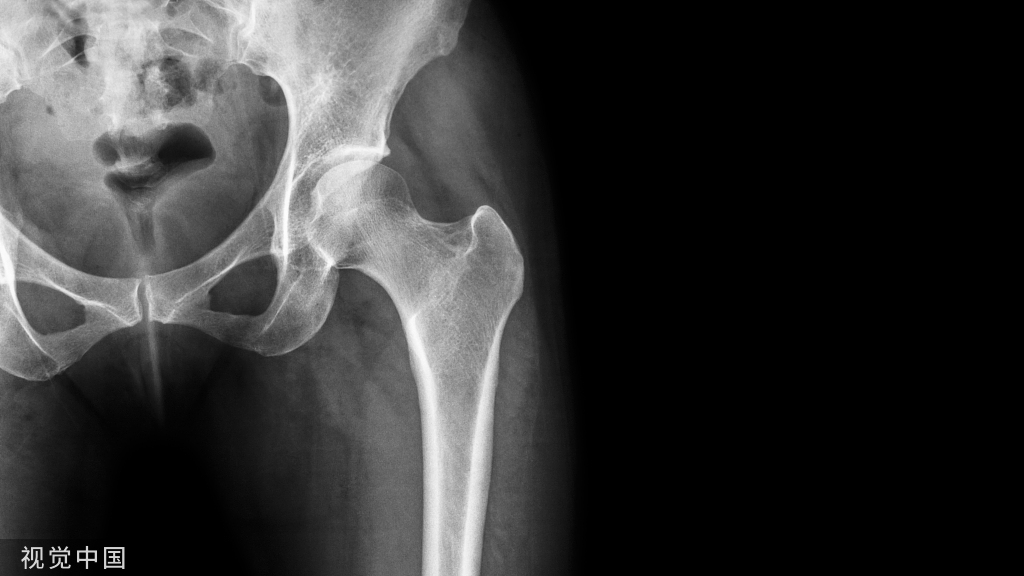

32、股骨颈骨皮质增厚

• 股骨颈骨皮质增厚,可能为滑膜囊下系带骨化所致。